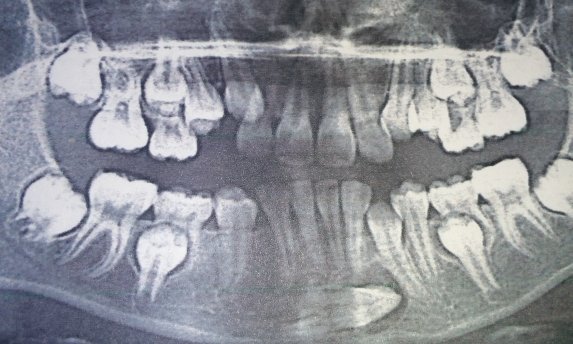

Дентальная галерея: ретинированный зуб клык и его лечение

Раздел: Компас решений